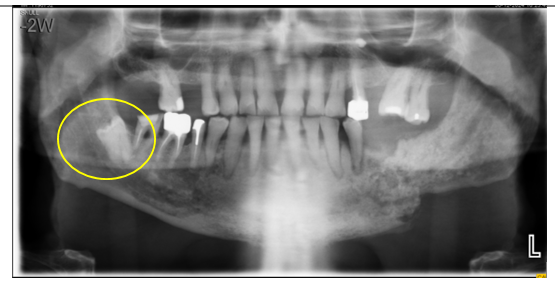

Our patient is an 80-year-old man, married, and the father of one son who died in a road traffic accident. He has a history of hypertension and diabetes, both well controlled with medical treatment. He was admitted to our department for the management of a solitary plasmacytoma of the mandible. The disease appears to have started approximately three months prior to admission, with the onset of localized swelling and dental mobility, prompting him to consult his dentist. A panoramic dental X-ray and a CT scan of the facial bones were performed, revealing a semi-recent left parasymphyseal mandibular fracture with significant mandibular osteocondensation and an associated anterior periosteal reaction. These findings were highly suggestive of chronic osteomyelitis complicating the aforementioned fracture. There was also evidence of phlegmon involving the soft tissues surrounding the left mandibular body in the area of the fracture, without any clearly organized collection.

Figure 1: Left mandibular osteolytic lesion on orthopantomogram in a patient with plasmacytoma.

Malignant plasma cells produce cytokines and release an osteoclast-activating factor that stimulates osteoclasts to resorb bone; consequently, on radiographic examination, they appear as well-defined osteolytic lesions with either unilocular or multilocular radiolucency (10,14). According to Lae et al., three radiographic patterns have been described in SBP: multilocular 'soap bubble' lesions, unilocular radiolucency (as seen in our patient) with a cystic appearance, and poorly defined destructive bone resorption (15). CT helps to refine the radiological image and assess the extension toward cortical and soft tissues. MRI remains a valuable imaging modality for detecting bone-involved plasmacytomas, assessing soft tissue involvement and bone marrow infiltration, and evaluating disease throughout the body. Solitary plasmacytomas show low signal intensity on T1-weighted images and high signal intensity on T2-weighted images, with homogeneous enhancement after gadolinium contrast injection (16).